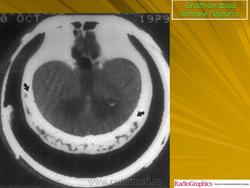

Бластная фаза

Принято различать три фазы развития П. б.: очаговая интенсивная резорбция кости (остеолитическая, или деструктивная, фаза), смешанная фаза, когда наряду с рассасыванием кости идут процессы новообразования ее, и остеобластическая, или склеротическая, фаза с образованием типичных мозаичных структур.